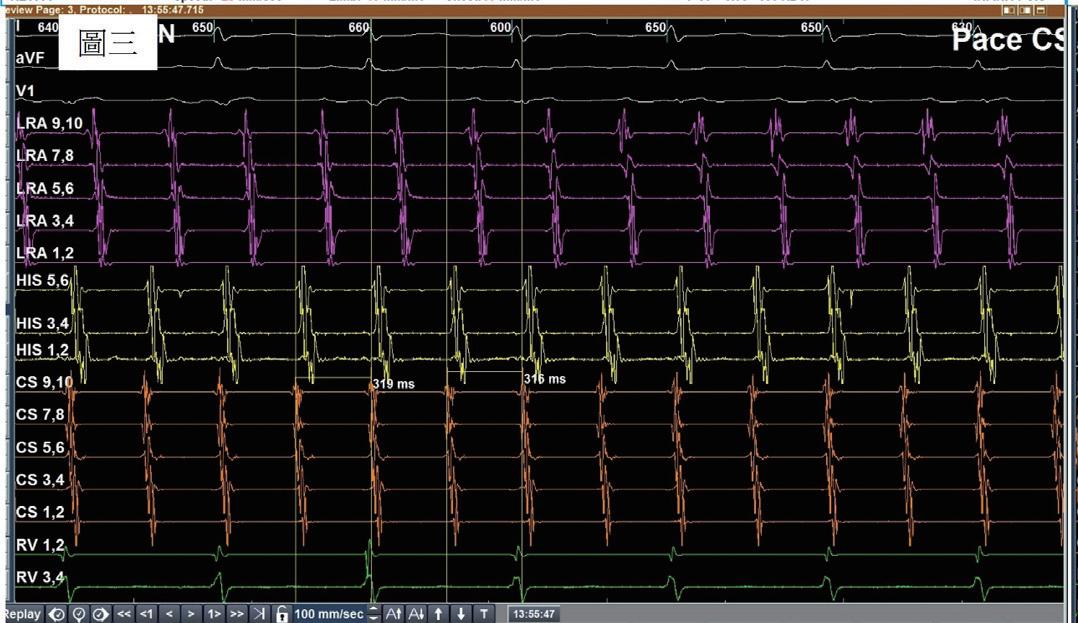

一位 76 歲女性,有高血壓以及陣發性心房顫動病史,規律於心臟科門診服用抗心律不整藥物 (flecainide) 以 及抗凝血劑 (apixaban) 以控制慢性病。然而,病人最近數月來感到間歇性胸悶與心悸,且症狀逐漸加重。經血 管介入專家排除冠狀動脈狹窄阻塞之問題後,判斷此病人之不適與多種嚴重心律不整有關 ( 如圖一與圖二 ) ,包 含可能源自於左心房的心房撲動 (atypical atrial flutters) 。經詳細解釋與討論,病人決定入院接受電氣生理檢查 與電氣燒灼治療。術前電腦斷層顯示左心房及左心耳無血栓,左心房有擴大 ( 約為 160 毫升 ) 。手術當日,病人心 律為 counter-clockwise isthmus-dependent atrial flutter( 如圖三 ) ,利用 entrainment method ,冠狀竇近端比遠端更 近 flutter circuit , 3 維傳播路徑圖為逆時針旋轉路徑。但是在 cavo-tricuspid isthmus 阻斷後, flutter 並未停止,發 生了訊號序列以及 cycle length 的變化,此時右側心房沒有辦法找到合適 entrainment 位置,經兩心房 3 維傳播路 徑圖判定病人之心律不整已轉變為源自左心房後壁之 atypical atrial flutter ,但是在左心房後壁阻斷後, flutter circuit 和 cycle length 仍不斷改變。在左心房經歷如同警匪追逐戰一般的多次阻斷以及訊號序列轉變後 ( 如圖四至 圖六 ) ,終於在冠狀竇 (coronary sinus) 遠端完成此病人的心律不整電氣燒灼手術 ( 如圖七 ) ,且無法再誘發。此病 人之心房撲動訊號序列變化與燒灼相關整理如圖八。術後病人恢復良好,胸悶心悸感已完全消除,固定於門診 領取抗凝血劑與低劑量抗心律不整藥物持續服用併追蹤。

(圖三)、

病人接受電氣燒灼手術當天的 baseline rhythm 。為一個 counter-clockwise atrial flutter。透過entrainment method得知冠狀 竇近端較冠狀竇遠端更靠近flutter circuit。